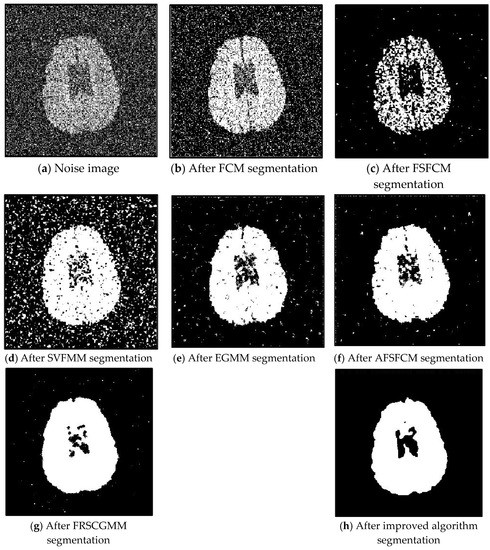

This paper addresses the lack of robustness of feature selection algorithms for fuzzy clustering segmentation with the Gaussian mixture model. Assuming that the neighbourhood pixels and the centre pixels obey the same distribution, a Markov method is introduced to construct the prior probability [...] Read more.

This paper addresses the lack of robustness of feature selection algorithms for fuzzy clustering segmentation with the Gaussian mixture model. Assuming that the neighbourhood pixels and the centre pixels obey the same distribution, a Markov method is introduced to construct the prior probability distribution and achieve the membership degree regularisation constraint for clustering sample points. Then, a noise smoothing factor is introduced to optimise the prior probability constraint. Second, a power index is constructed by combining the classification membership degree and prior probability since the Kullback–Leibler (KL) divergence of the noise smoothing factor is used to supervise the prior probability; this probability is embedded into Fuzzy Superpixels Fuzzy C-means (FSFCM) as a regular factor. This paper proposes a fuzzy clustering image segmentation algorithm based on an adaptive feature selection Gaussian mixture model with neighbourhood information constraints. To verify the segmentation performance and anti-noise robustness of the improved algorithm, the fuzzy C-means clustering algorithm Fuzzy C-means (FCM), FSFCM, Spatially Variant Finite Mixture Model (SVFMM), EGFMM, extended Gaussian mixture model (EGMM), adaptive feature selection robust fuzzy clustering segmentation algorithm (AFSFCM), fast and robust spatially constrained Gaussian mixture model (GMM) for image segmentation (FRSCGMM), and improve method are used to segment grey images containing Gaussian noise, salt-and-pepper noise, multiplicative noise and mixed noise. The peak signal-to-noise ratio (PSNR) and the error rate (MCR) are used as the theoretical basis for assessing the segmentation results. The improved algorithm indicators proposed in this paper are optimised. The improved algorithm yields increases of 0.1272–12.9803 dB, 1.5501–13.4396 dB, 1.9113–11.2613 dB and 1.0233–10.2804 dB over the other methods, and the Misclassification rate (MSR) decreases by 0.32–37.32%, 5.02–41.05%, 0.3–21.79% and 0.9–30.95% compared to that with the other algorithms. It is verified that the segmentation results of the improved algorithm have good regional consistency and strong anti-noise robustness, and they meet the needs of noisy image segmentation. Full article